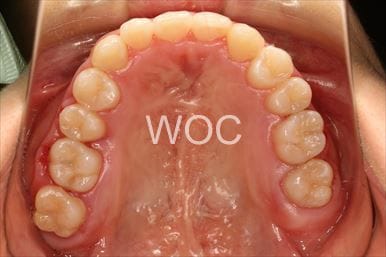

治療中1

治療中2

治療中3

治療中4

治療中5

- 年齢:17歳女性

- 主訴:出っ歯、前歯のガタガタが気になる

- 基本矯正料金:78万円

- 治療期間:1年2ヶ月

- 抜歯部位:上顎両側第一小臼歯